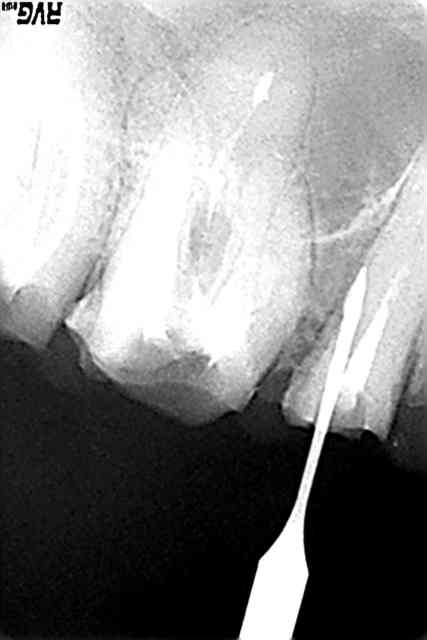

Pour obturer les canaux, il faut les aléser, c’est à dire les élargir et régulariser leur paroi interne. On utilise pour cela des instruments rotatifs proches des forets . Si un canal est coudé, il arrive que l’instrument ne suive pas la coudure et continue à forer dans une mauvaise direction. Ceci s’appelle une fausse route et aboutit à la création d’un faux canal.

Parfois, c’est lors du forage d’un logement pour pivot que la fausse route se produit.

Le diagnostic est facile à faire: les perforations saignent énormément et il faut systématiquement y penser devant une hémorragie endopulpaire. La radio avec des sondes radio opaques en place confirme généralement la perforation.